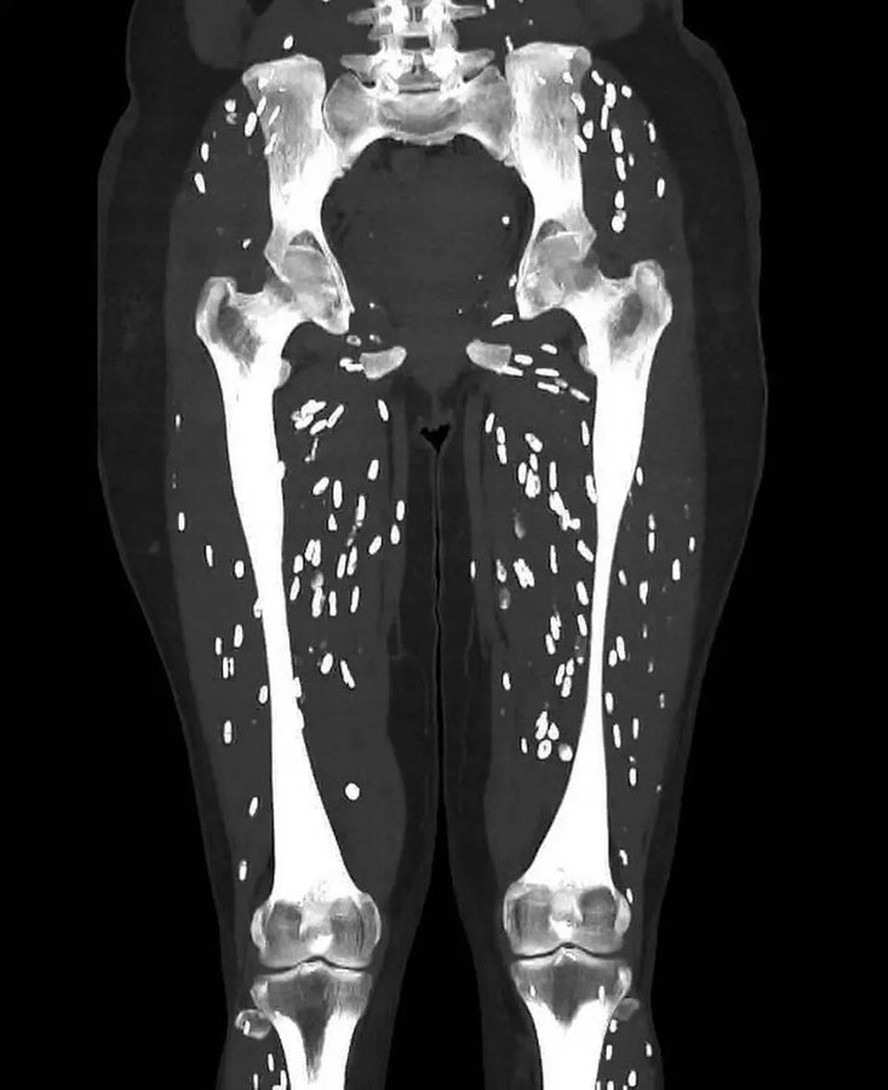

Médico usa raio-x de paciente infestado de ovos de tênia e pede atenção no preparo de carne de porco; entenda — Foto: Reprodução

Com mais de seis milhões de visualizações,o médico de atendimento de urgência da Universidade da Flórida Sam Ghali usou uma publicação no X para falar sobre o risco de exposição à cisticercose pelo consumo de carne de porco mal cozida. A doença parasitária ocorre pelo contato com fezes humanas infectadas com o ovo da tênia através de alimentos,água ou superfícies contaminadas com fezes. Os humanos engolem os ovos quando comem alimentos contaminados ou colocam os dedos contaminados na boca.

Na postagem,Ghali diz que a imagem anexada é de um dos exames mais inacreditáveis que ele já viu. O médico aproveita para compartilhar com seus seguidores mais detalhes do processo de infecção,sintomas comuns e o que pode ocorrer em caso de negligência. Veja a publicação abaixo:

"Os humanos são infectados ao ingerir cistos que podem ser encontrados em carne de porco mal cozida. Após várias semanas (geralmente em torno de 5 a 12),esses cistos evoluem dentro do trato gastrointestinal para tênias adultas maduras. Essa condição é conhecida como Teníase Intestinal. Essas tênias adultas então eliminam ovos excretados nas fezes humanas. Depois que os ovos são ingeridos (humanos ou porcos),eles liberam larvas que penetram na parede intestinal e invadem a corrente sanguínea e de lá podem se espalhar para literalmente qualquer lugar do corpo inteiro. O cérebro,os olhos,os tecidos subcutâneos e os músculos esqueléticos são os destinos mais comuns. As larvas se alojam onde quer que acabem e,por fim,formam cistos conhecidos como cisticercos",detalhou Ghali.

Considerada rara no Brasil,com menos de 150 mil casos por ano,a cisticercose é causada por cistos da larva da Taenia solium nos tecidos. Cisto é uma forma que protege certos protozoários,com uma película ou cápsula,envolvendo um parasita capaz de se reproduzir quando encontrar o ambiente adequado.